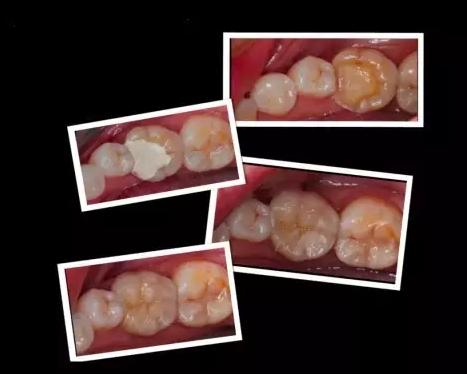

嵌体和传统的补牙不同之处是:嵌体是在口外石膏模型上由专门的牙科技师制作出来的,然后再由临床医生将其戴入患者口内,最终粘固形成的。

1、因为它的整个制作过程是在口外完成的,所以它还可以很好的恢复原来牙齿的外形,恢复原来牙齿的咀嚼效率。而这一点,是传统补牙无论如何都无法比拟的。

这些嵌体,在最终戴如患者口内的时候,真是的非常的完美。在使用上没有任何的影响和不适,而且坚固耐用。做嵌体修复的时候,好的材质也对嵌体的修复效果产生影响。

那么,你为什么不试一试呢?这些嵌体,在最终戴入患者口内的时候,都是非常完美的,在使用上没有任何的影响和不适,而且坚固耐用。